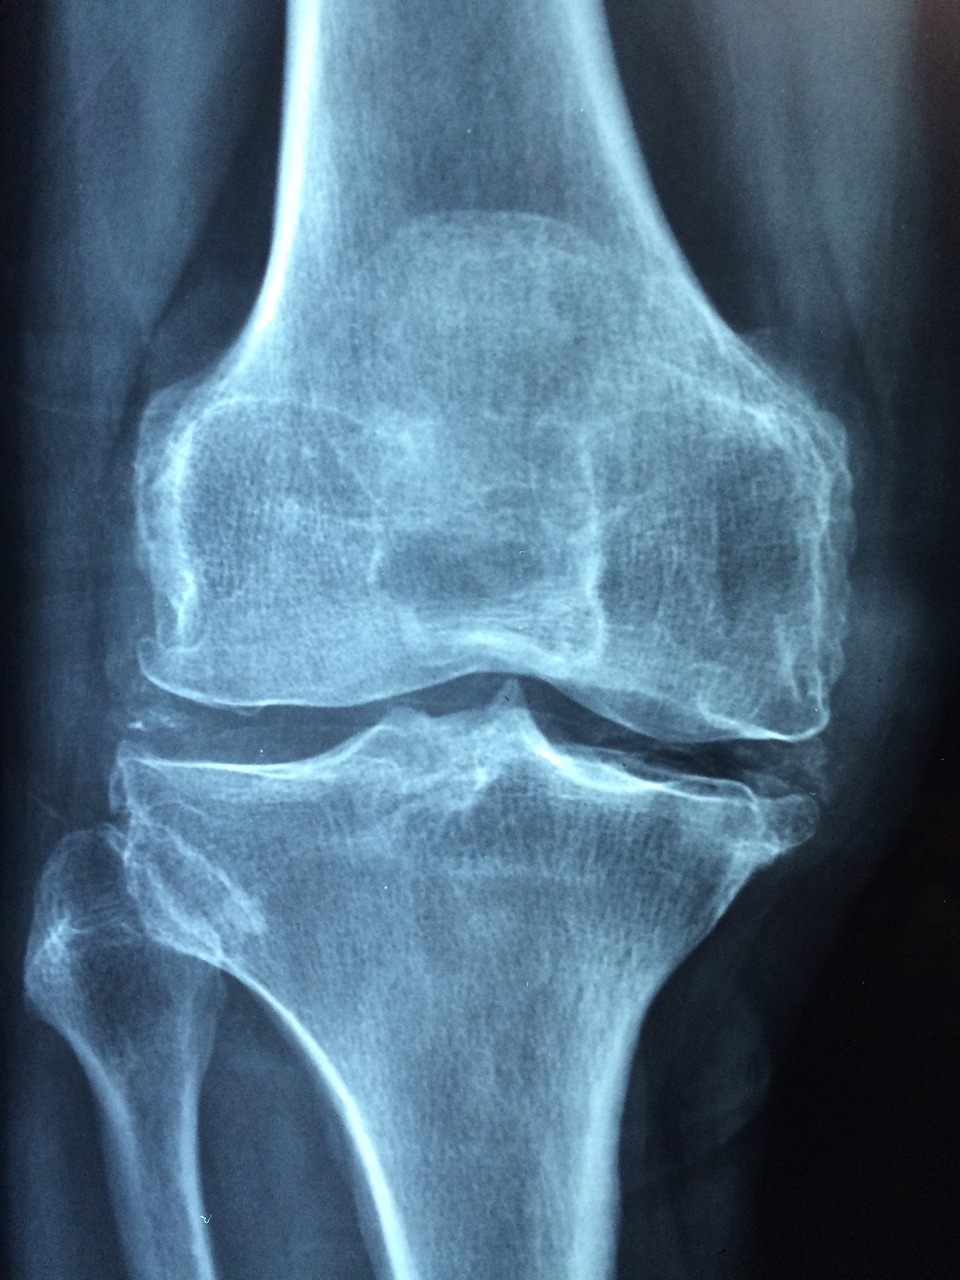

골다공증은 뼈가 약해져 골절에 더 취약해지는 것이 특징인 질환입니다. 사전 발견은 골다공증을 효과적으로 관리하고 치료하는 데 매우 중요합니다. 이 구성은 골다공증을 진단하는 데 사용되는 다채로운 유형의 검사와 스타일을 탐구하여 뼈 건강의 이러한 중요한 측면을 이해하고자 하는 사람들에게 상세한 분석을 제공합니다. 골다공증은 자주 조용히 진행되며, 골절이 발생하기 전까지 수많은 사람들이 그 상태에 대해 무지합니다. 무증상 특성을 감안할 때, 조기에 정확한 의견은 효과적인 수술과 합병증 예방에 필수적입니다. 이 블로그 게시물은 골다공증을 진단하는 데 사용되는 다양한 유형의 검사, 관련된 스타일 및 이러한 검사 중에 예상할 수 있는 사례를 살펴볼 것입니다. 이러한 개별 도구를 이해함으로써, 개인들은 뼈 건강을 유지하고 골다공증의 관류 상품을 배제하는 데 선견지명을 가질 수 있습니다. 골미네랄 점도(BMD) 테스트 골미네랄 점도(BMD) 검사는 골다공증 의견의 기초입니다. 가장 일반적이고 광범위하게 받아들여지는 골미네랄성 검사는 이진 에너지 X선 흡수 측정(DEXA 또는 DXA) 검사입니다. DEXA 검사는 턱뼈, 둔부 또는 팔뚝의 뼈 점도를 측정하여 골절 위협에 대한 정확한 평가를 제공합니다. 시술 중에, 환자는 패딩 처리된 테이블 위에 놓여 있으며, 낮은 큐어 X선은 뼈를 통과합니다. 이 검사는 빠르고, 비침습적이며, 힘들이지 않으며, 일반적으로 약 10에서 20번의 반짝임이 걸립니다. 결과는 T-점수로 보고되며, 이는 환자의 뼈 점도를 건강한 젊은 성인의 뼈 점도와 비교합니다. -1.0 또는 그 이상의 T-점수는 정상으로 간주되며, -1.0과 -2.5 사이는 골감소증(낮은 뼈 점도)을 나타내며, -2.5 또는 그 이하는 골다공증을 확인합니다. BMD 테스트의 또 다른 시스템은 발뒤꿈치의 뼈 점도를 측정하는 정량적 초음파(QUS)입니다. 이 시스템은 이동성이 뛰어나고 가격이 저렴하며 방사선을 사용하지 않습니다. QUS는 DEXA 리뷰보다 정확도가 낮지만 원본 와이어 또는 DEXA를 사용할 수 없는 환경에 자주 사용됩니다. DEXA 검진을 통해 더 많은 평가가 필요할 수 있는 위협에 처한 개인을 식별하는 데 도움이 됩니다. 보충 정량적 기록 단층 촬영(pQCT)은 팔뚝의 뼈 점도를 측정하는 데 주로 사용되는 또 다른 BMD 테스트 시스템입니다. DEXA와 달리 pQCT는 3차원 영상을 제공하고 피질(경질) 뼈와 섬유질(해면질) 뼈를 분리할 수 있습니다. 이 테스트는 덜 일반적으로 사용되지만 특정 임상 스크립트에서 소중한 지각력을 제공할 수 있습니다. 생화학적 마커 테스트 생화학적 마커 테스트는 뼈 발달 속도를 반영하는 혈액 또는 소변의 특정 물질의 상황을 측정합니다. 이러한 테스트는 뼈의 형태와 재흡수의 동적 과정에 대한 정보를 제공하여 골절 위협과 검사자 치료 효율을 평가하는 데 도움이 됩니다. 혈청 C-텔로펩티드(CTX) 및 소변 N-텔로펩티드(NTX)와 유사한 라벨은 뼈 흡수를 나타내는 반면 혈청 프로콜라겐 유형 I N 프로펩티드(PINP)와 오스테오칼신은 뼈의 형태를 반영합니다. 재흡수 라벨의 높은 상황은 골다공증에서 흔히 볼 수 있는 뼈 손실 증가를 시사합니다. 이러한 테스트는 의견에 대한 명확성은 낮지만 치료 반응 및 불만 진행을 다루는 데 유용합니다. 생화학적 라벨은 BMD의 변화보다 뼈 대사의 변화를 더 신속하게 감지하여 치료 효율을 조기에 평가할 수 있는 장점을 제공합니다. 그럼에도 불구하고 나이, 코이투스, 일주기 측정 및 최근 음식 입력과 유사한 다채로운 요인으로 설명할 수 있어 해석이 더 복잡해집니다. 따라서 다른 개인 스타일과의 융합에서 자주 사용됩니다. 기술의 발전은 생화학적 라벨의 섬세함과 연결을 지속적으로 완벽하게 만들고 있습니다. 뼈 건강에 대한 더 구체적이고 신뢰할 수 있는 정보를 제공할 수 있는 새로운 라벨을 식별하기 위한 연구가 진행 중이며, 잠재적으로 골다공증 수술에서 더 개별화된 접근 방식으로 이어질 수 있습니다. 척추 골절 평가(VFA) 및 기타 영상 방법 척추 골절은 골다공증이 있는 개인에게 흔하며 최소한의 외상이나 외상 없이도 가능합니다. 이러한 골절을 감지하는 것은 후방 골절의 위협을 크게 증가시키고 심각한 뼈 약화를 나타내기 때문에 매우 중요합니다. VFA는 DEXA 검진 중에 수행되는 X선 영상의 기술적 형태입니다. 임상 검사 또는 표준 X선을 통해 분명하지 않을 수 있는 골절을 식별하기 위해 중국의 이미지를 캡처합니다. VFA는 척추 골절이 진단되지 않은 경우가 많지만 환자 건강에 대한 심각한 역고발이 있기 때문에 포괄적인 골다공증 평가를 위한 소중한 도구입니다. 화려한 공명 영상(MRI) 및 기록된 단층 촬영(CT) 리뷰는 뼈 건강을 평가하고 골절을 묘사하는 데에도 사용될 수 있습니다. MRI는 뼈와 거딩 소프트 앱킨의 자세한 이미지를 제공하며, 척추 골절로 인한 척수 수축과 유사한 합병증을 평가하는 데 유용합니다. CT 리뷰는 고해상도 이미지를 제공하고 뼈 점도를 정량화할 수 있지만 일반적으로 DEXA 리뷰에 비해 고급 비용 및 방사선 노출로 인해 복잡한 경우에 사용이 제한됩니다. 이러한 이미징 방법은 귀중한 정보를 제공하지만 일반적으로 주요 개별 스타일보다는 상호 도구로 사용됩니다. 비용이 많이 들 수 있으며 모든 임상 환경에서 쉽게 사용할 수 없을 수도 있습니다. 그럼에도 불구하고 골절이 의심되거나 복잡한 뼈 상태가 있는 경우 이러한 고급 이미징 양식이 필요합니다. 골다공증의 정확한 의견은 BMD 테스트, 생화학적 마커 테스트 및 고급 이미징 방법의 조합을 포함합니다. 각 개별 도구의 강점과 한계를 이해하는 것은 골다공증의 효과적인 운영과 치료에 필수적입니다. 이러한 테스트를 통한 사전 발견은 개인이 뼈 건강을 보장하고 이 조용한 불만과 관련된 심각한 결과를 돕기 위한 선견지명적 조치를 취하는 데 도움이 될 수 있습니다. 정보를 유지하고 적용 가능한 테스트를 모색함으로써 사례는 의료 제공자와 협력하여 강하고 건강한 뼈를 유지하기 위한 실질적인 전략을 개발할 수 있습니다.